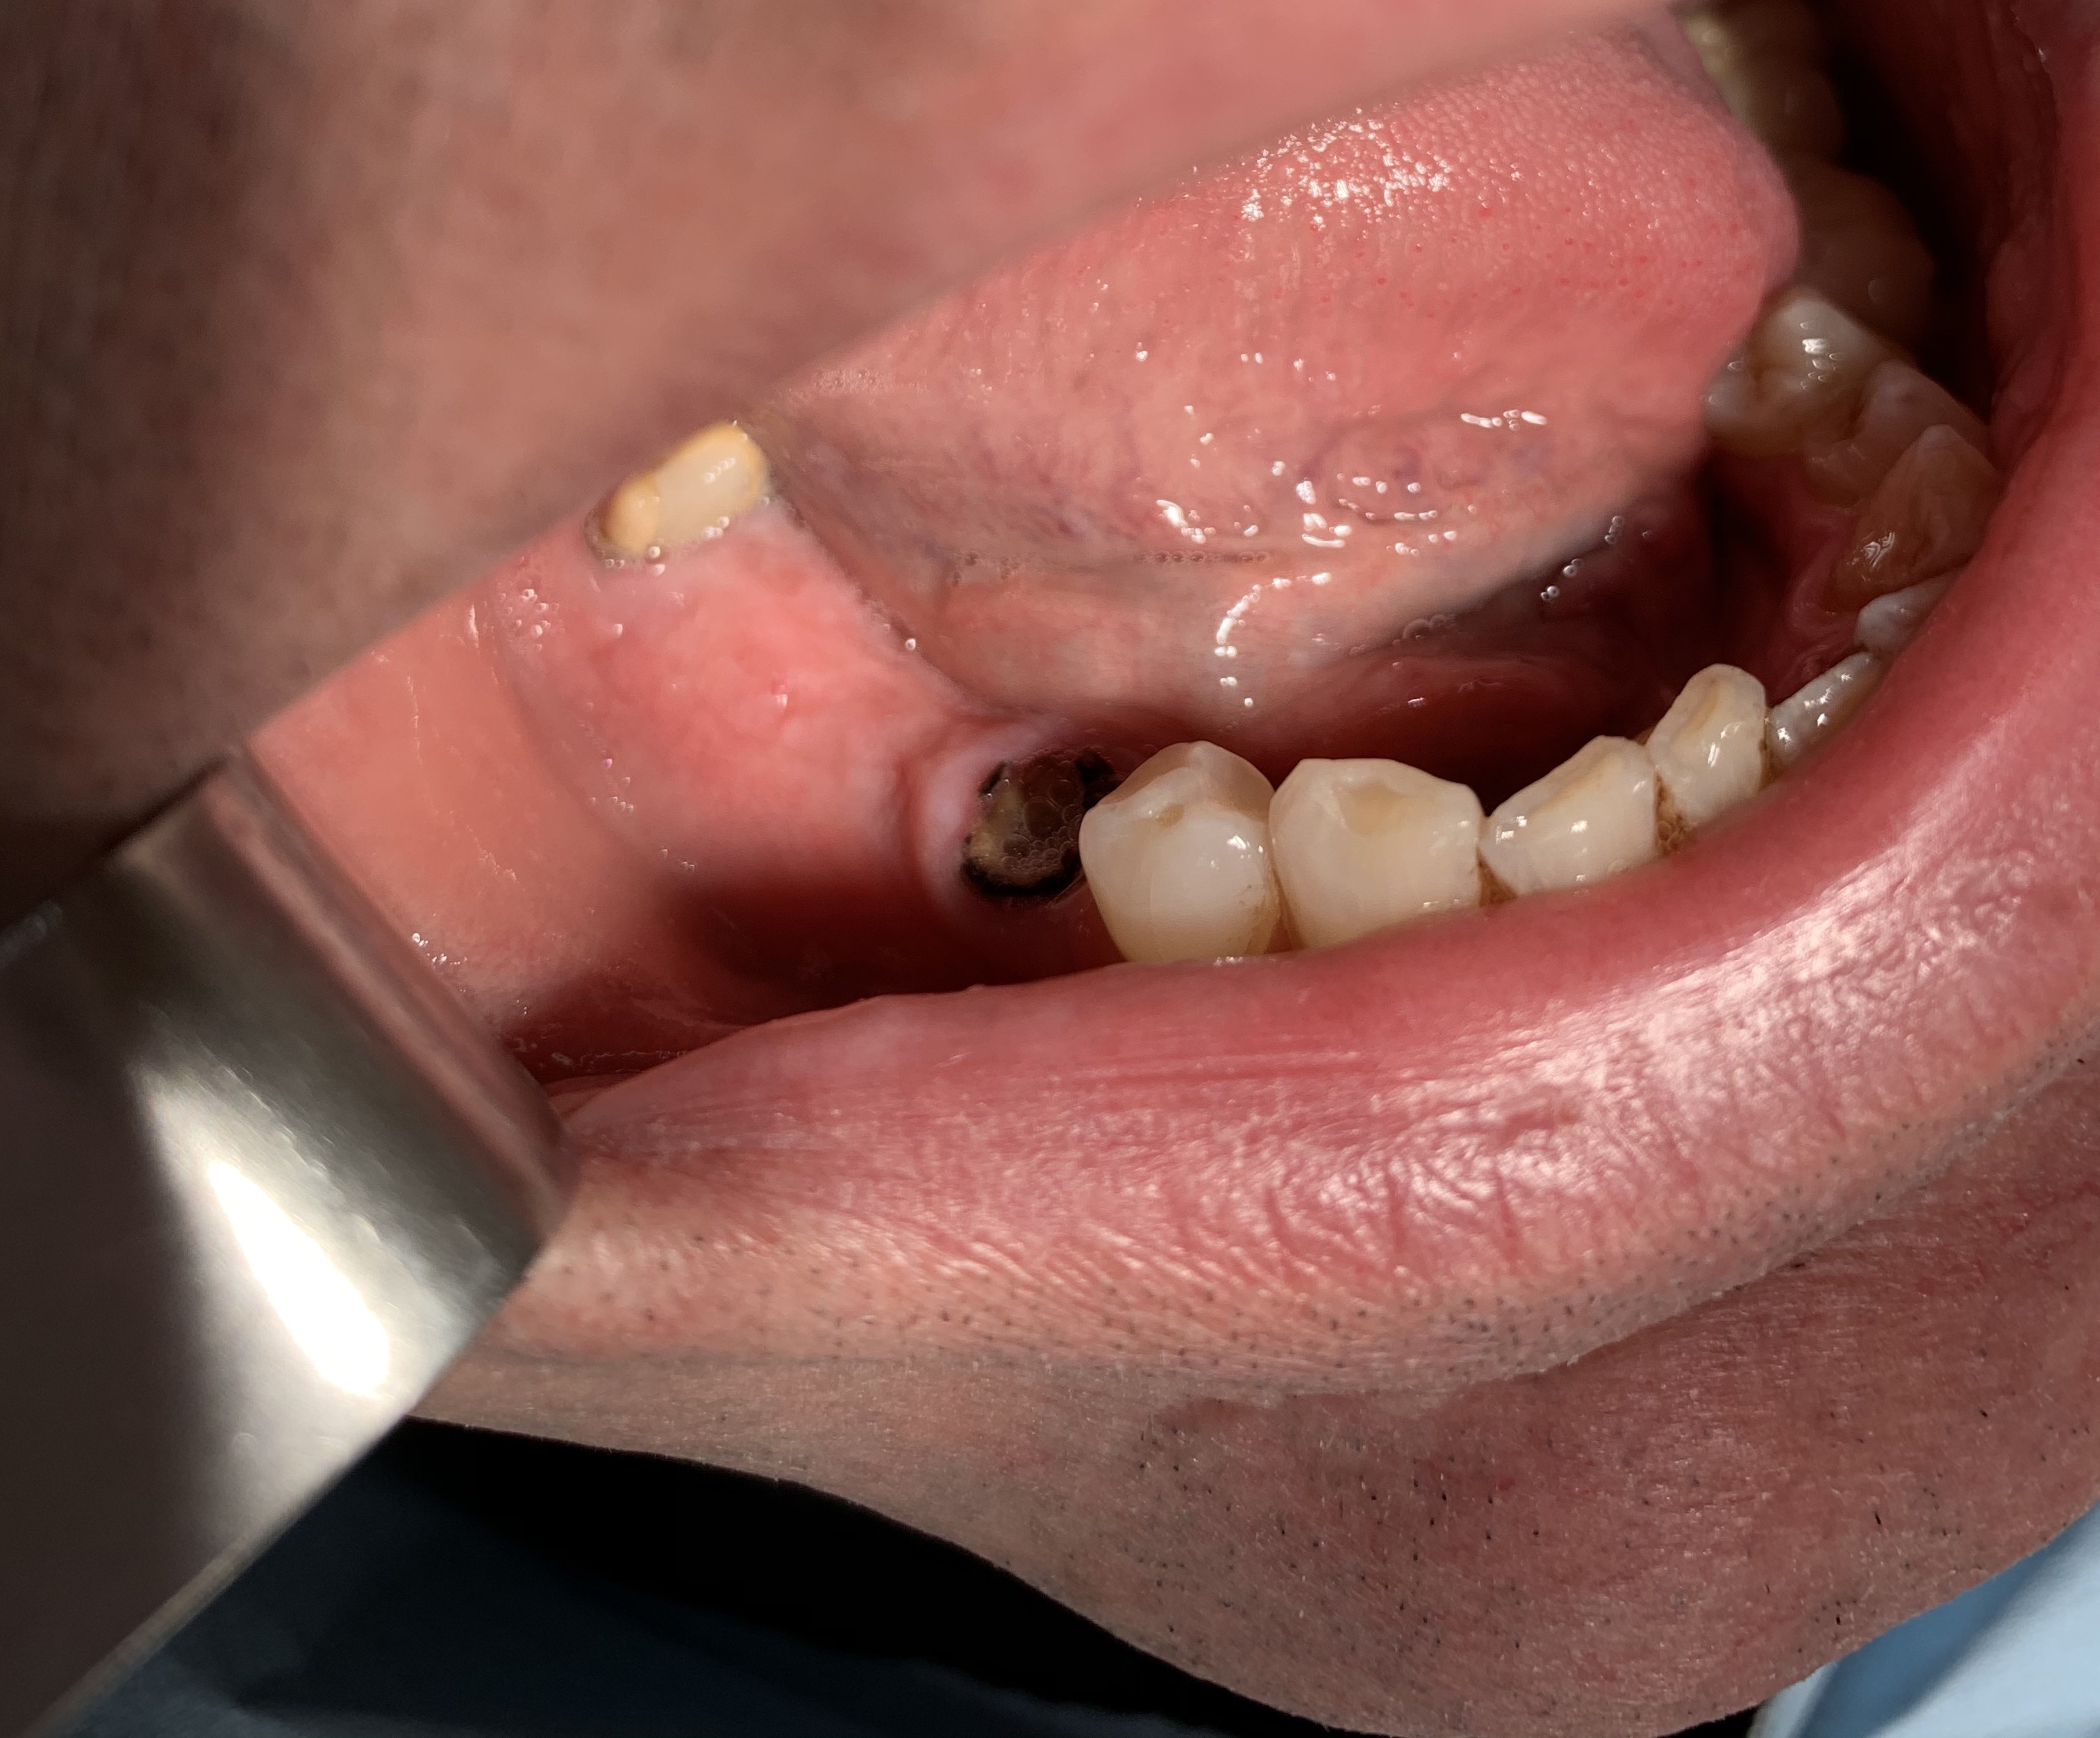

4 - IMPIANTO DI TRAMONTE IN ETA' AVANZATA

Un paziente con impianti italiani da 28 anni ha bisogno ancora di impianti ma ora ha quasi novanta anni e prende molte medicine.